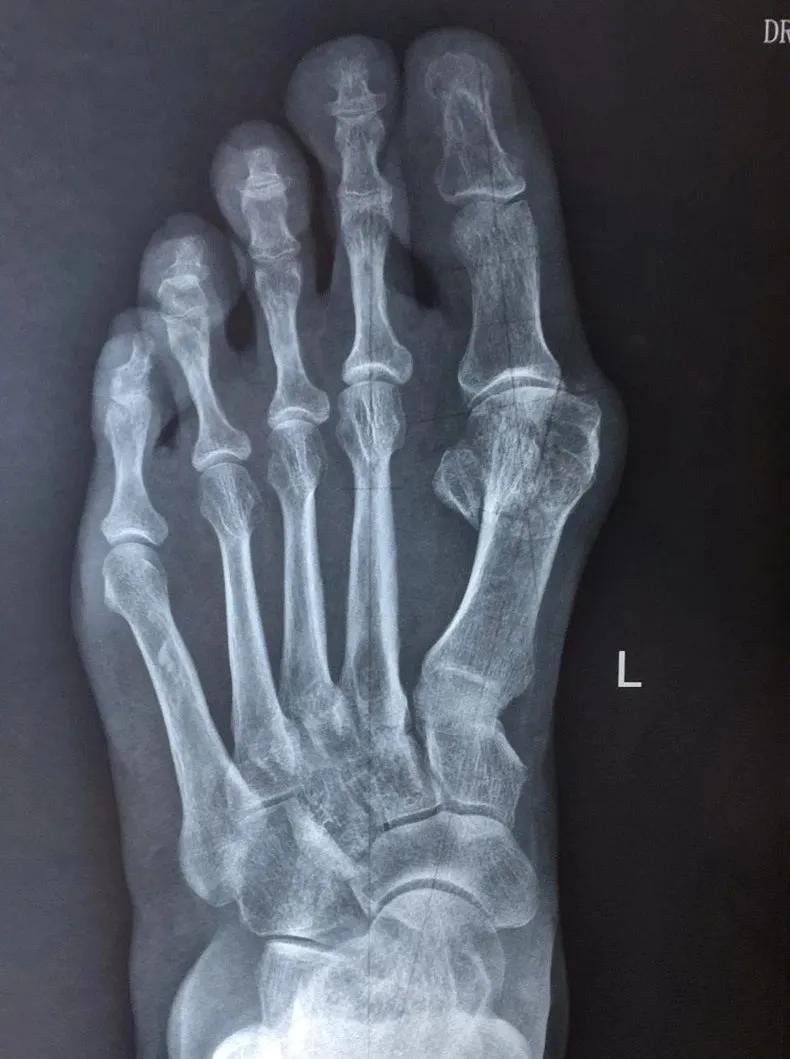

入院后,通过对患者双足负重下的正侧位X片的足趾畸形力线研究分析,经该院骨科科室医师讨论后,认为朱阿姨左右足虽然都是踇外翻畸形,实际病变畸形情况却有所不同:其左足转移性第2、3跖骨头疼痛明显,但前足5个跖骨头生理弧度相对较好,故采用踇外翻改良Chevron截骨矫形术;右足踇外翻畸形相对较轻,但影像学表现上第一跖骨长度较第二跖骨短缩明显,前足5个跖骨头生理弧度改变,为预防日后右足症状加重,故采用标准的Scarf截骨矫形术。

段连杰医生根据朱阿姨病情解释道:踇外翻患者的影像学表现和临床症状体征有时并不完全一致,有些患者是因为“大脚骨”位置疼痛来就医;有些则是因为足底第2、3跖骨头位置疼痛而来;或者是因为足趾爪型改变穿鞋时磨脚疼痛就诊;有些患者足趾外观畸形改变严重,但临床疼痛症状轻;而有些人看着足趾畸形表现不重,却行走时疼痛难忍。

该住院患者的影像学表现踇外翻畸形不大,但患者出现了明显的转移性跖骨痛,且双足的第一跖骨长度不等,故采用2种不同术式治疗,这也是目前国内外学术界普遍认为踇外翻标准化治疗的最佳方案。